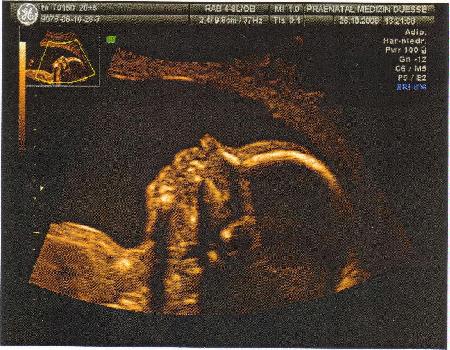

21.Woche